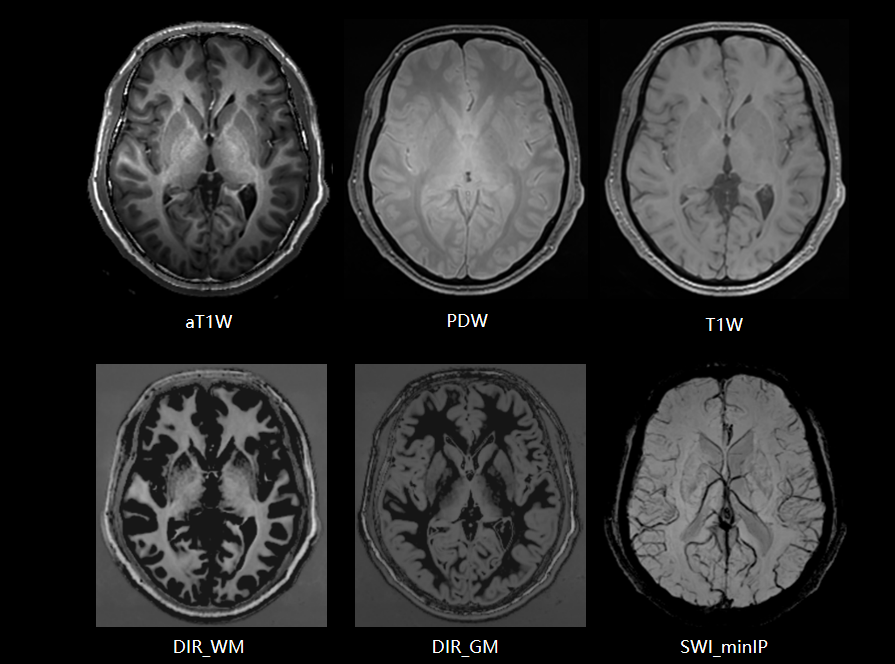

搭载uAIFI Technology技术平台,凝聚多项全球首创核心技术,全链条革新磁共振硬件、软件设计,实现系统性能、扫描智能化、成像速度与信噪比的大幅提升,同时赋予患者更舒适的检查体验,开启磁共振“类脑”时代。

新一代数字化射频系统,实现单视野单次扫描最高达72+通道成像。

联影第二代高密线圈,全身成像密度提升超过50%